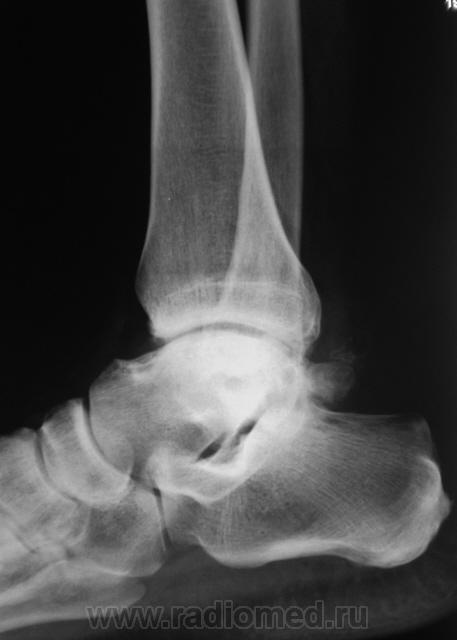

Пациент направлен на рентгенографию голеностопного сустава с диагнозом ДОА.

После внутрисуставного перелома вероятность доа оччень высока. Колгда была травма?

Травма была два года тому.

Похоже  на  остеохондропатию  блока  таранной  кости  +   ДОА.

А присутствует линейный (или лентовидный, я их путаю) остеопороз, а это признак острого процесса.

+ за лентовидный остеопроз...

Будем думать, что некроз блока таранной кости не такой уж и асептический, какая-то инхвекция там есть.

Посттравматический артроз с кистовидной перестройкойлатерального мыщелка Субхондральное уплотнение исужение суст. щелей естьИ неконгруэнтность большеберцового эпифиза к таранной маленько просматривается?